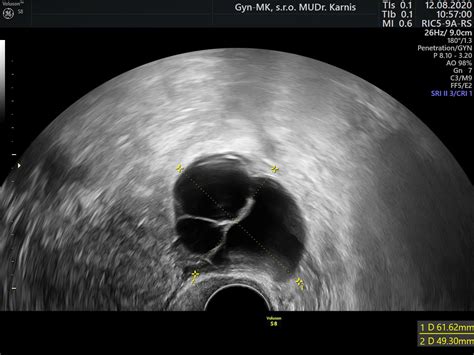

Nasleduje vlastná stimulácia vaječníkov dávkou hormónov v podobe HMG (ľudský menopauzálny gonadotropín) alebo FSH (folikuly stimulujúci hormón). V priebehu hormonálnej stimulácie, ktorá trvá jeden až tri týždne, dochádza k ultrazvukovej kontrole zrejúcich folikulov z dôvodu stanovenia vhodného času na odber vajíčok. Pokiaľ sú vytvorené ideálne podmienky, začne sa pomocou injekcií hCG (ľudský choriový gonadotropín) vyvolávať ovulácie.

Niektoré páry užívajú na podporu plodnosti rôzne bylinné čaje ešte pred návštevou centra. Zo samotnej hormonálnej stimulácie môžu mať ženy strach, predovšetkým z predstavy každodennej aplikácie injekcií. Partnerova podpora je v tomto prípade kľúčová. Stimulácia môže trvať približne 14 dní, pričom v prvých dňoch nemusí organizmus na liečbu reagovať a je potrebné zvýšiť dávku. Pri poslednom ultrazvuku sa podávajú lieky na spustenie ovulácie a 36 hodín po injekcii nasleduje odber vajíčok.

Následný odber vajíčok prebieha pod ultrazvukovou kontrolou a je presne načasovaný. Zákrok zvyčajne trvá 10 minút a robí sa v celkovej anestézii. Počas odberu sa prepichne stena pošvy, ihla sa dostane do brušnej dutiny a napichne sa vaječník. Po odsati vajíčok sa postup opakuje na druhej strane.